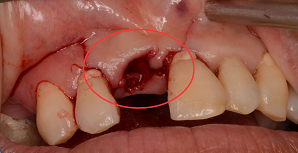

牙齿的缺损,如果不及时就诊治疗修复,不仅会失去此牙齿,造成其他牙齿的过早松动,影响咀嚼,肠胃消化吸收,面貌美观受损。后期再要治疗花费也会更高。